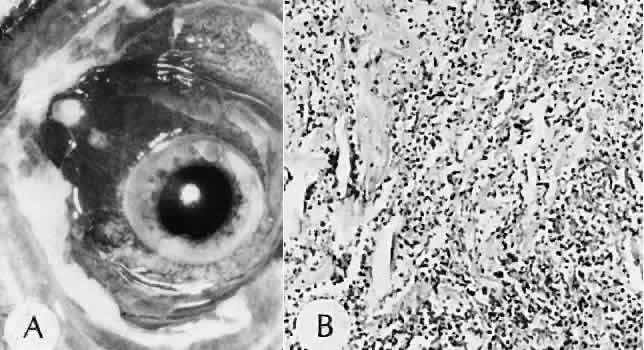

Granulation tissue often is the first type of reparative tissue in wound healing (Fig. 1). Although its composition varies somewhat, small-caliber vascular channels in a delicate collagenous stroma infiltrated by acute and chronic inflammatory cells generally characterize it. This amorphous tissue serves as a template for more definitive repair.

Fig. 1. Granulation tissue. A. Clinical photograph of granulation tissue (often mistakenly called a pyogenic granuloma) at the site of a ruptured chalazion. B. Granulation tissue growth in the region of a chalazion. The tissue has responded by forming multiple fine-caliber vascular channels associated with an infiltrate of acute and chronic inflammatory cells. The lightly stained areas in the tissue represent the response of fibroblasts and vascular endothelial cells to alter and augment the extracellular matrix. (Hematoxylin-eosin stain; × 100.)